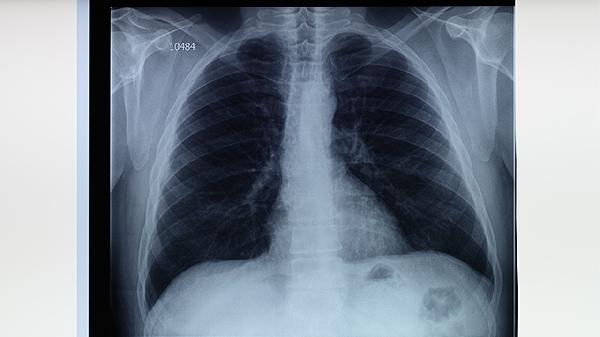

肺結(jié)核患者常感到胸部隱痛或刺痛,深呼吸或咳嗽時(shí)疼痛加重。胸痛多位于病變部位,可能與胸膜受累或肺部炎癥刺激有關(guān)。部分患者還可出現(xiàn)肩部或背部牽涉痛。胸痛程度與病情嚴(yán)重性相關(guān),需通過影像學(xué)檢查明確病因。